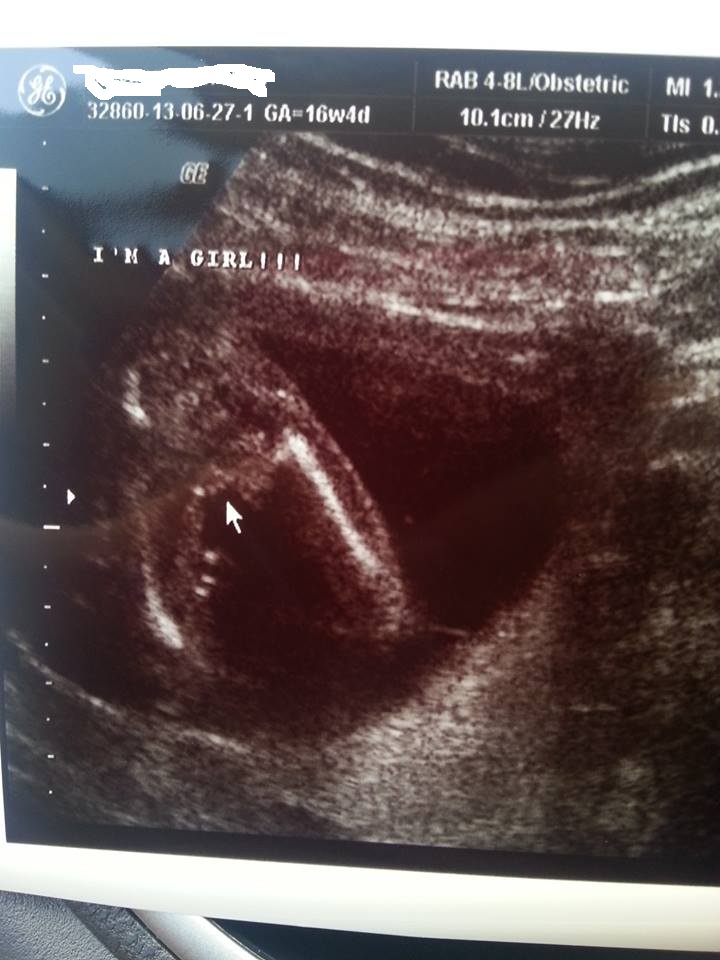

congratz, was this your 20 week scan or 16?

The top one is 16w 4d and the bottom is 20 weeks and 3 days